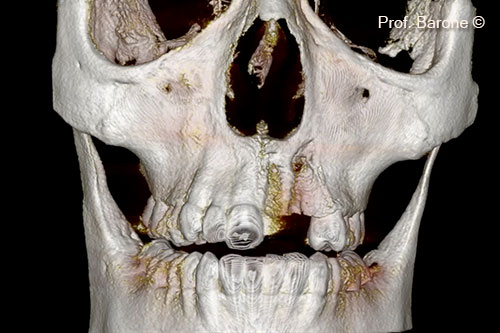

Một bệnh nhân nữ trẻ (19 tuổi) có khuyết tật rộng theo chiều ngang và chiều dọc.

Răng bị mất (21, 22, 23) một phần đáng kể xương môi đã bị mất

Toàn bộ xương môi đã biến mất. Khuyết tật rộng 16mm, cao 15mm, sâu 5mm

Hình ảnh 3D thể hiện mô ghép và các vật cấy ghép đã được đặt